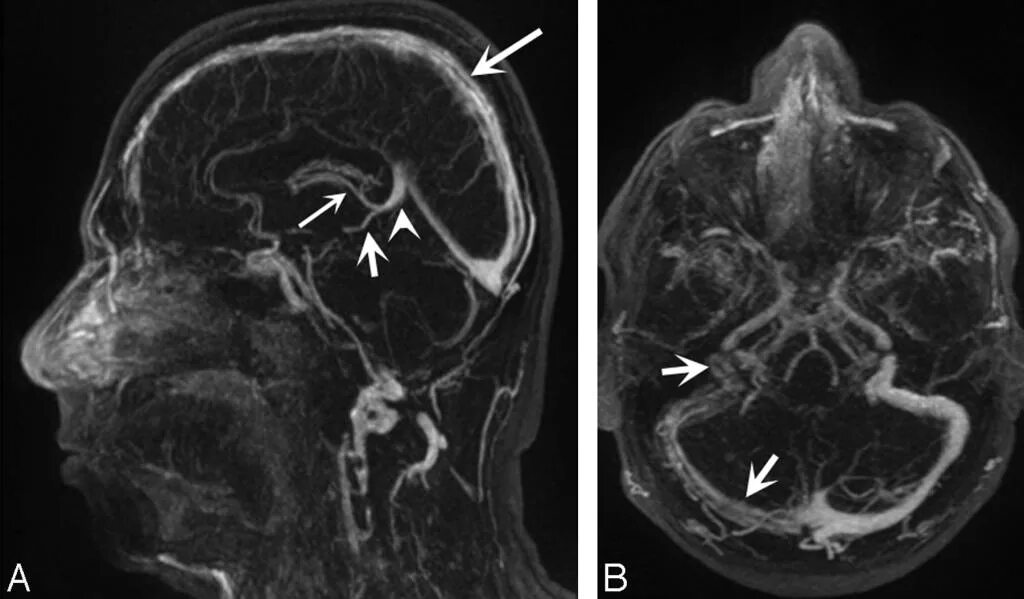

Что покажет мрт головного мозга с контрастом